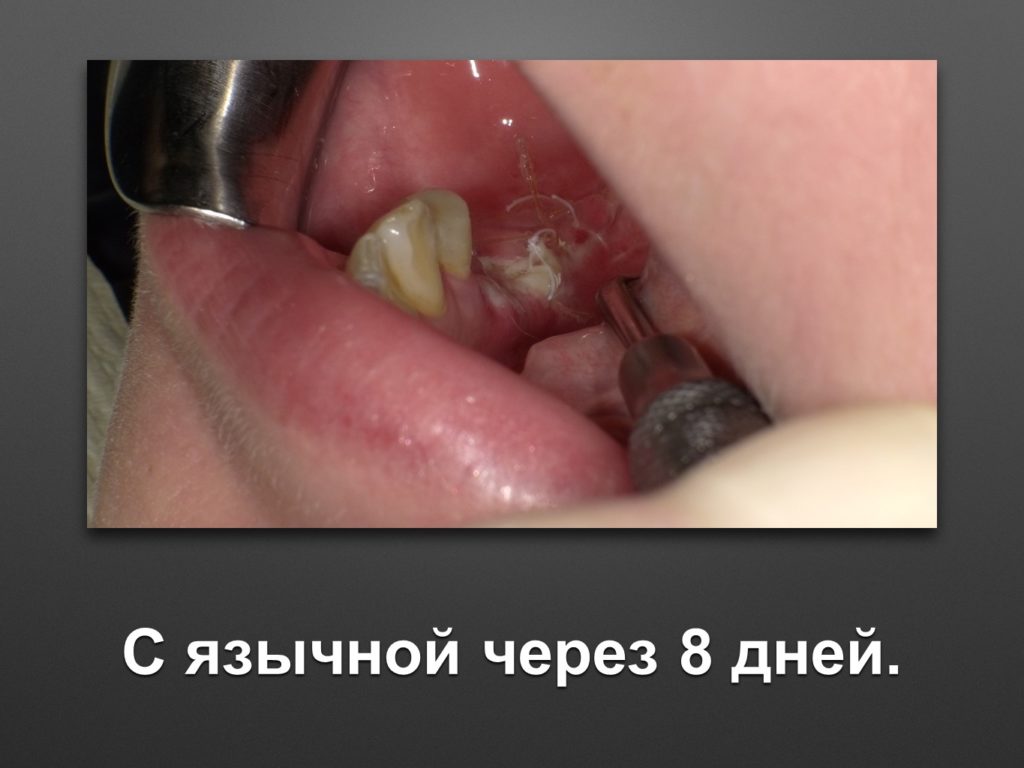

Горизонтальное увеличение альвеолярного отростка н/ч